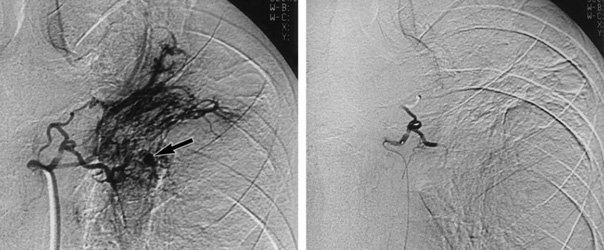

The aim of the procedure is to stop the blood flowing into the arteries which are responsible for haemoptysis while preserving blood flow to the normal surrounding area. The interventional radiologist will insert a less than 2 mm tube into your groin and will guide it under imaging to the affected blood vessel. Small resin particles (microparticles) will be inserted into the bleeding abnormal vessel or vessels in case of bronchial arteries. This causes the vessel or vessels to become blocked and so stops the bleeding. In case of pulmonary artery pathology coils, vascular plugs or liquid embolic agent may be used.